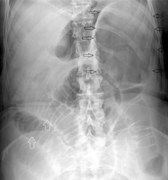

Normal

Normal